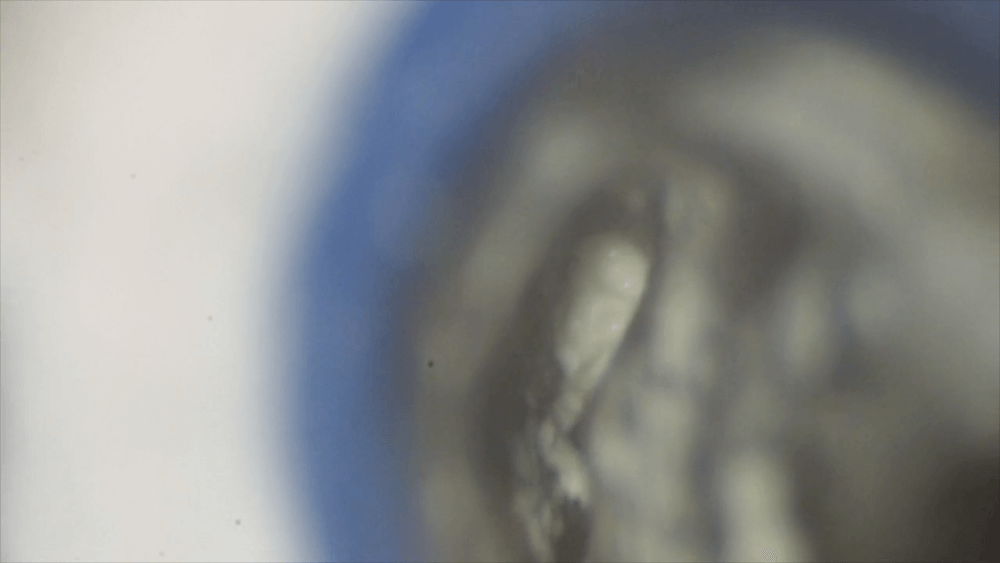

もう片方の根管はガッタパーチャポイントにて根管充填を行います。

術後のレントゲン写真です。

樋状根はとても複雑な形態の根管であり、そのため、治療も複雑になります。そのため、マイクロスコープを用いた根管治療が必須になります。この複雑な根管から、肉眼で細菌感染を取り除くのは至難の技でしょう。